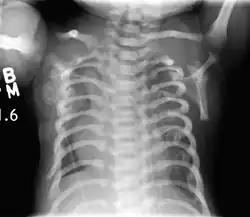

| CXR of a newborn with asphyxiating thoracic dysplasia. Note the short ribs. | |

| Symptoms | Narrow chest, short ribs, shortened bones of the arms and legs, unusually shaped pelvis, and extra fingers and/or toes |